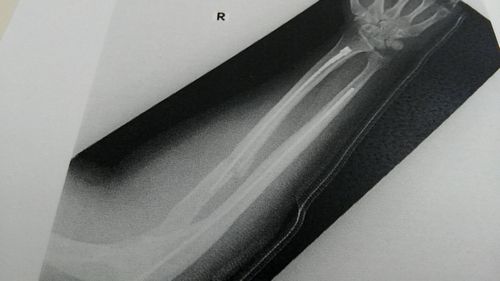

腕にかなり長いチタンの棒が二本入りました。

分かりづらいですが、術後はこんな感じ。

上も下も折れてますが、下は合わせてもらってます。

上の骨が損傷激しいので、超音波治療器を渡されました。

超音波を当てて、骨の治癒力を高めるというロストテクノロジー!